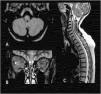

To describe the magnetic resonance imaging (MRI) findings for the most common inflammatory and immune-mediated diseases that involve the brainstem.

ConclusionInflammatory lesions involving the brainstem are associated with a wide range of autoimmune, infectious, and paraneoplastic syndromes, making the differential diagnosis complex. Being familiar with these entities, their clinical characteristics, and their manifestations on MRI, especially the number of lesions, their shape and extension, and their appearance in different sequences, is useful for orienting the radiological diagnosis.